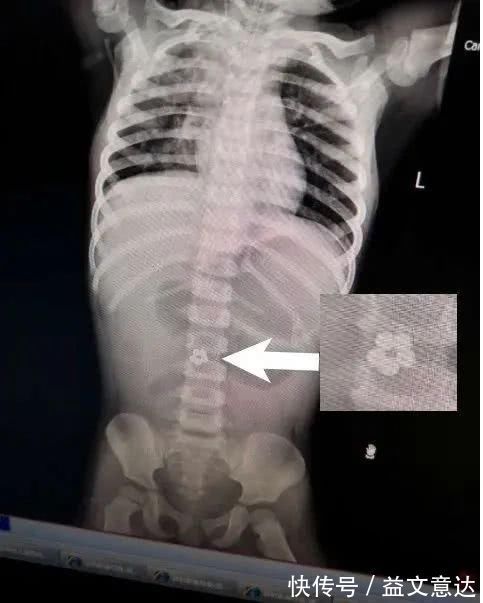

拍片检查的结果

让大家都惊呆了

在静静肚子里

居然发现有5个连成圈的小球!

文章插图

(X光检查发现,小静腹中有5颗小球)